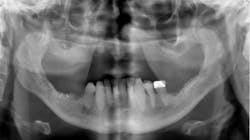

Who provides the informed consent information (see figure 2 above)

Although dentists are the ones legally responsible for the informed consent, educated staff members can provide this information, with the dentist coming in at the end of the consultation and summarizing it.